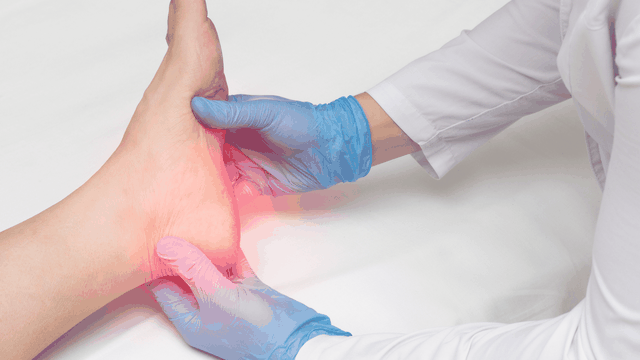

Bong gân có thể xảy ra ở bất cứ ai và ở bất kỳ bộ phận nào của cơ thể nhưng thường gặp nhất ở chi trên và chi dưới. Vậy các khớp nào thường bị bong gân? Bài viết dưới đây sẽ tổng hợp các vị trí thường bị bong gân cũng như cách nhận biết khi gặp tình trạng này.